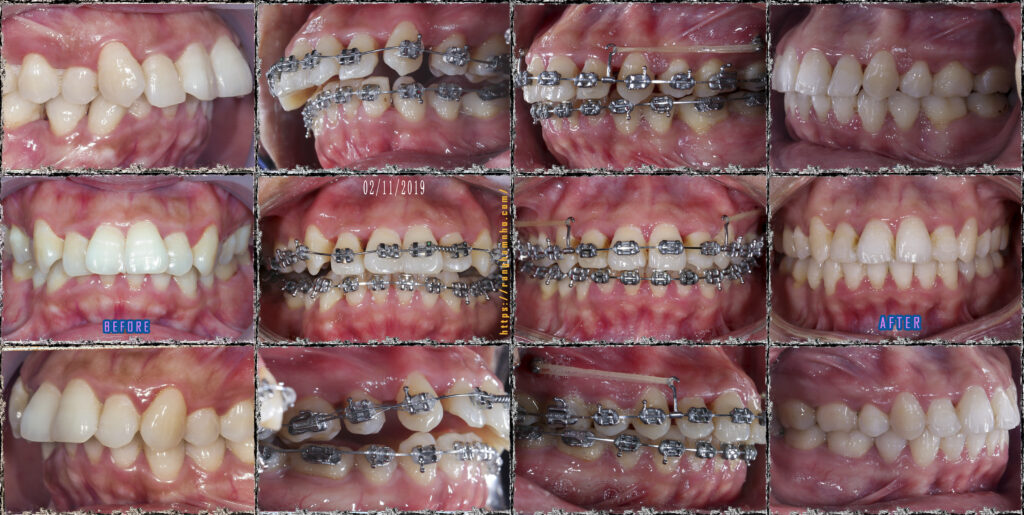

BN sinh năm 1987, đến phòng khám với than phiền hô, nụ cười khấp khểnh, răng chen chúc nhiều. Qua thăm khám đây là một trường hợp hô khá nặng kết hợp cả hô do răng và hô do xương. Nếu mong muốn cải thiện 100% thì BN cần phẫu thuật, cài thiện sau niềng răng đơn thuần chỉ đạt 60-70%.

BN chọn niềng răng đơn thuần với chỉ định nhổ 4 răng số 4, có neo chặn hỗ trợ bằng 2 minivis ở hàm trên.

Sau 2 năm đeo niềng, kết quả trục răng đã thay đổi rất tích cực, tình trạng khớp cắn sâu cũng đã được giải quyết triệt để. Nụ cười cải thiện rõ rệt so với trước niềng.